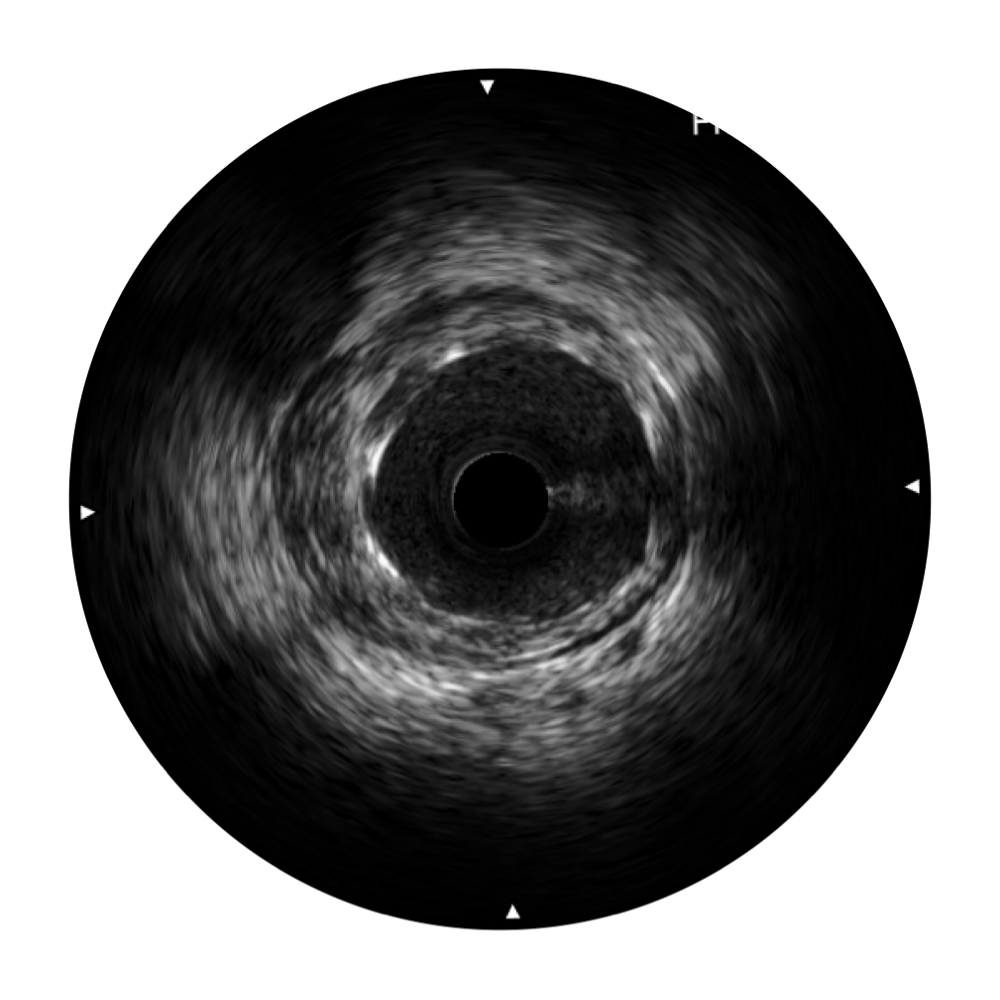

• 玖鼎集团宽频IVUS图像

对比传统IVUS导管成像,玖鼎集团宽频IVUS图像的近场支架梁显影更细腻,远场中膜外血管仍清晰可辨,兼顾远中近,兼顾分辨力与穿透深度